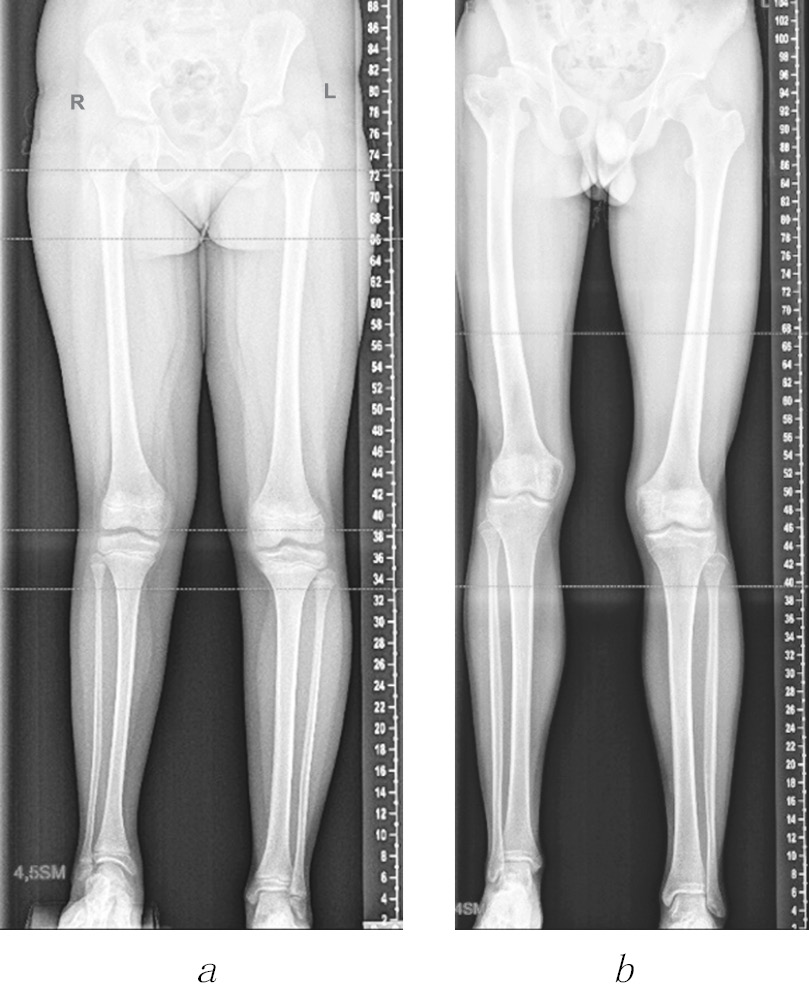

The patient records and results of radiation examination of the main groups of pediatric patients were analyzed. Group 1 was the control group, and group 2 included 11 pediatric patients aged 8 to 16 years (mean age, 11.9 ± 1.05 years) with congenital shortening of the lower extremity and hypofunction of metaepiphyseal epiphyseal cartilage of the femur and tibia. The degree of involvement in the pathological process of the epiphyseal zones of the affected extremities was not evaluated. The average difference in the length of the lower extremities was Δl = 4.8 ± 0.80 cm (Fig. 1, a). Group 3 included 11 patients aged 9 to 16 years (mean age, 12.2 ± 0.78 years) with acquired shortening of the lower extremity with destructive changes in the proximal metaepiphyseal femoral growth zone after acute hematogenous osteomyelitis. The average difference in the length of the lower extremities was Δl = 4.5 ± 0.38 cm due to the shortening of the femoral length (Fig. 1, b). Patients of both groups had hypotrophy of the soft tissues of the thigh and lower leg of the affected extremity of varying severity.

Fig. 1. Panoramic radiographs of the lower extremities: a — patient K., 10 years old, with congenital shortening of the right lower extremity by 4.5 cm; b — patient A., 16 years old, with acquired shortening of the right lower extremity by 4.0 cm